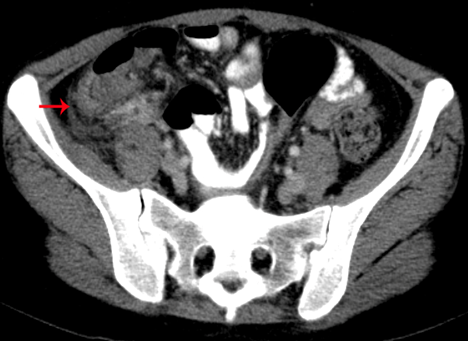

Abb.1: Neutropene Enterokolitis im Zökum (Typhlitis). Zirkuläre Wandverdickung (Pfeil) mit Reaktion des umliegenden Gewebes.